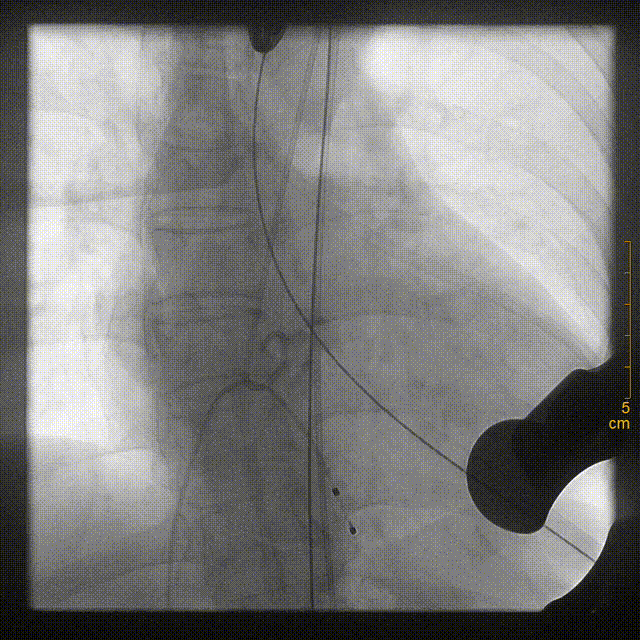

将装置好J-Valve23mm主动脉瓣的输送鞘送至主动脉瓣瓣环平面,释放定位装置并造影定位

稳定释放瓣膜

严重钙化使瓣膜形态未完全展开

球囊扩张后,瓣膜形态完美,超声复查无瓣周漏,冠脉开口无堵塞